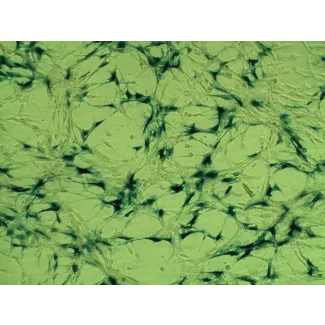

肺间质中最丰富的细胞类型是成纤维细胞。它们类似于普通的成纤维细胞,但具有一些独特的特征,例如长的分支过程和间隙连接。HPF的主要功能是合成III型胶原蛋白、弹性蛋白和肺泡隔膜的细胞外基质糖胺聚糖。肺成纤维细胞(PF)在损伤后的修复和重塑过程中起着重要作用。成纤维细胞在炎症部位的受控积累对损伤后的有效组织修复至关重要。成纤维细胞积累不足或过度积累都可能导致组织功能异常。例如,成纤维细胞的过度增殖有助于观察到的低氧引起的肺动脉高血压发展过程中的外膜增厚。

HPF来自ScienCell Research Laboratories,分离自人类肺组织。HPF在第一代细胞时被冻结保存,并以冷冻状态交付。每个小瓶包含>5 x 105个细胞,体积为1毫升。HPF通过特异性抗纤维连接蛋白抗体进行免疫荧光鉴定。HPF对HIV-1、HBV、HCV、支原体、细菌、酵母和真菌均为阴性。HPF在ScienCell Research Laboratories提供的条件下,保证进一步扩增15代。